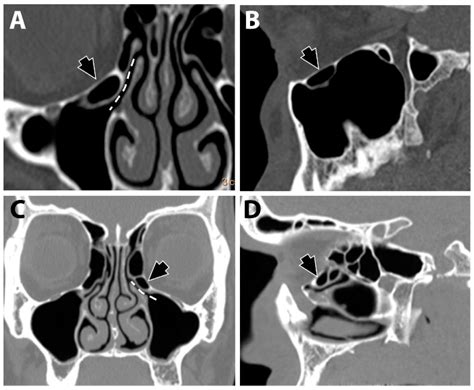

A Mxailliary Sinus CT scan, or Computed Tomography scan, is a non-invasive imaging procedure that uses X-rays to create detailed cross-sectional images of the sinuses. These images help doctors to identify abnormalities, infections, or structural issues within the sinuses. The scan is particularly useful for diagnosing conditions such as sinusitis, nasal polyps, and tumors.

The Mxailliary Sinus CT scan works by taking multiple X-ray images from different angles around the body. These images are then processed by a computer to create cross-sectional views of the sinuses. The resulting images provide a detailed view of the sinus cavities, allowing doctors to identify any abnormalities.

The results of a Mxailliary Sinus CT scan are interpreted by a radiologist, who will look for signs of:

• Inflammation: Swelling or infection in the sinuses.

• Obstruction: Blockages in the sinus passages.

• Abnormal Growths: Polyps, tumors, or other growths.

• Structural Issues: Deviated septum or other structural abnormalities.

Common Findings in a Mxailliary Sinus CT Scan

Some common findings in a Mxailliary Sinus CT scan include:

• Sinusitis: Inflammation of the sinuses, often due to infection.

• Nasal Polyps: Benign growths in the nasal passages.

• Tumors: Abnormal growths that may be benign or malignant.

• Fractures: Bone fractures in the sinus area, often due to trauma.

• Deviated Septum: A misaligned nasal septum that can cause obstruction.